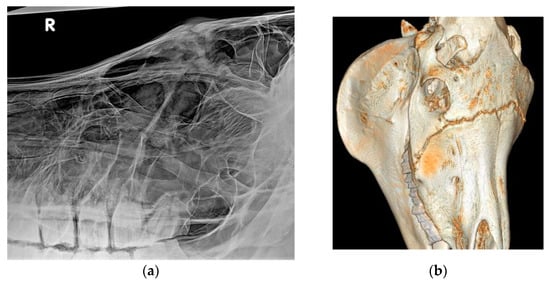

3.2. Imaging Findings